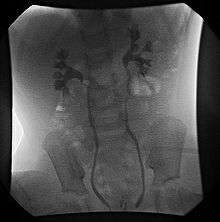

International Classification of Vesicoureteral Reflux

- Grade I – reflux into non-dilated ureter

- Grade II – reflux into the renal pelvis and calyces without dilatation

- Grade III – mild/moderate dilatation of the ureter, renal pelvis and calyces with minimal blunting of the fornices

- Grade IV – dilation of the renal pelvis and calyces with moderate ureteral tortuosity

- Grade V – gross dilatation of the ureter, pelvis and calyces; ureteral tortuosity; loss of papillary impressions

The younger the age of the patient and the lower the grade at presentation the higher the chance of spontaneous resolution. Most (approx. 85%) of grade I & II cases of VUR will resolve spontaneously. Approximately 50% of grade III cases and a lower percentage of higher grades will also resolve spontaneously.

- Fluoroscopic voiding cystourethrogram (VCUG)

VCUG is the method of choice for grading and initial workup, while RNC is preferred for subsequent evaluations as there is less exposure to radiation. A high index of suspicion should be attached to any case where a child presents with a urinary tract infection, and anatomical causes should be excluded. A VCUG and abdominal ultrasound should be performed in these cases